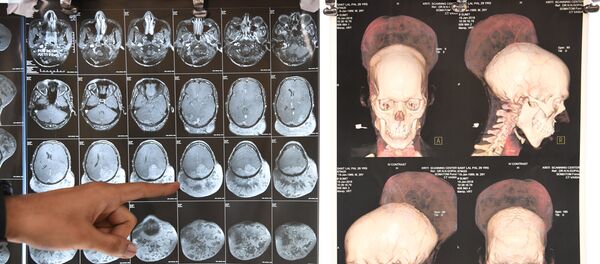

When the unidentified man first arrived at the ER, doctors didn't realize what they were dealing with until they took an x-ray of the injury.

Imaging revealed that the potentially explosive part of a mortar-type firework had ended up in his right thigh. The patient told the doctors that the firework didn't explode when he first attempted to set it off. When he tried to reload the device a second time, he heard an explosion.